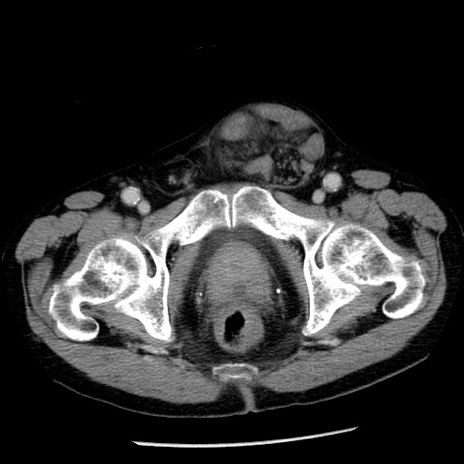

症例26(横断像)

【症例】80歳代男性

【主訴】嘔吐

【現病歴】昨晩2回嘔吐あり、今朝になっても嘔吐あり。来院。

【既往歴】胃潰瘍

【身体所見】意識清明、BT 37.6℃、BP 166/95mmHg、HR 100bpm、SpO2 97%、腹部:平坦・軟、腸蠕動音聴取良好、圧痛なし。

【データ】WBC 21900、CRP 1.46